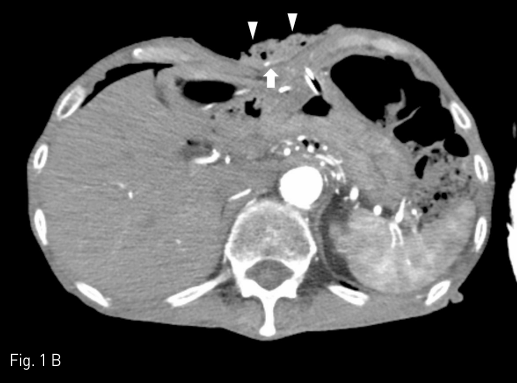

Contrast-enhanced CT study was performed to find out the presence of active bleeding. Comparing the pre-contrast (A) and arterial phase (B) images, contrast extravasation (arrow) between the skin and the packing gauze (arrowheads) is noted around the gastrostomy site.

Fig 1B